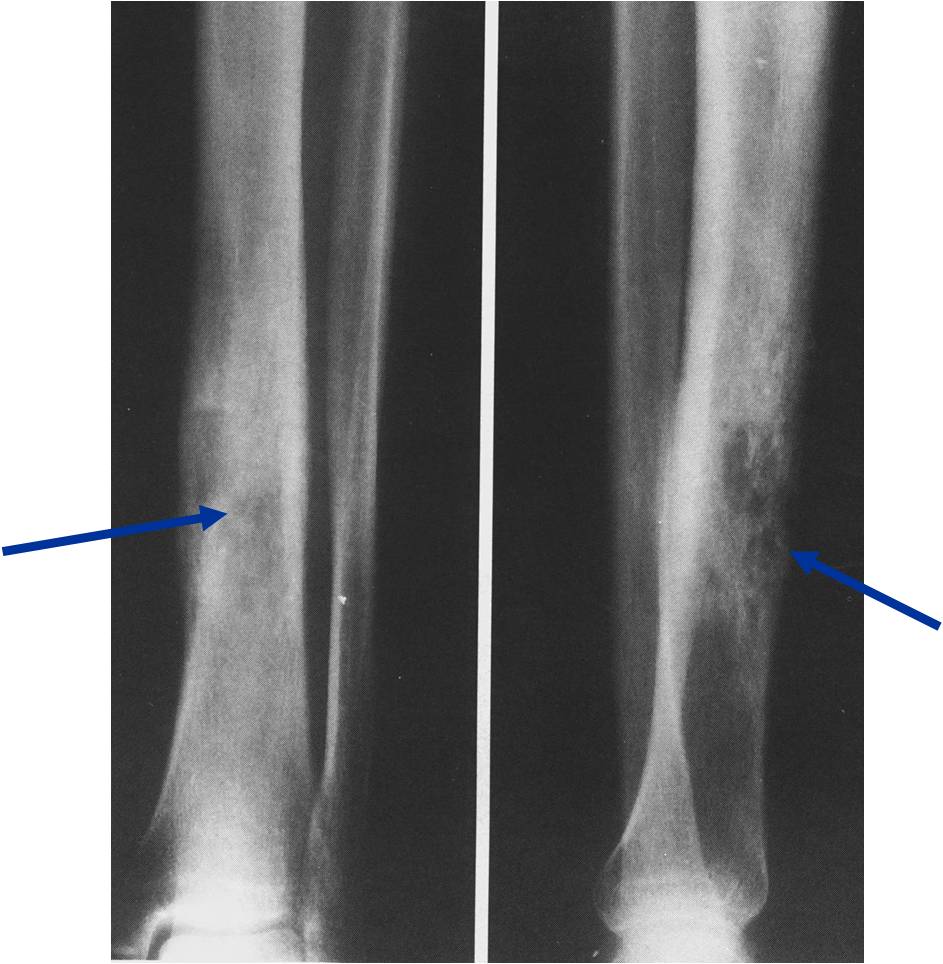

Permeative Moth eaten Lesion

Permeative Lesion

Permeative/Moth eaten lesion Reactive sclerosis (mixed lysis and sclerosis) Slight periosteal reaction

- Permeative or moth eaten bone destruction (55%)

- Geographic (11%); Blow out (1%); Blastic (2%); Normal XR (5%)

- Metadiaphysis (75%)

- Periosteal reaction—may look benign